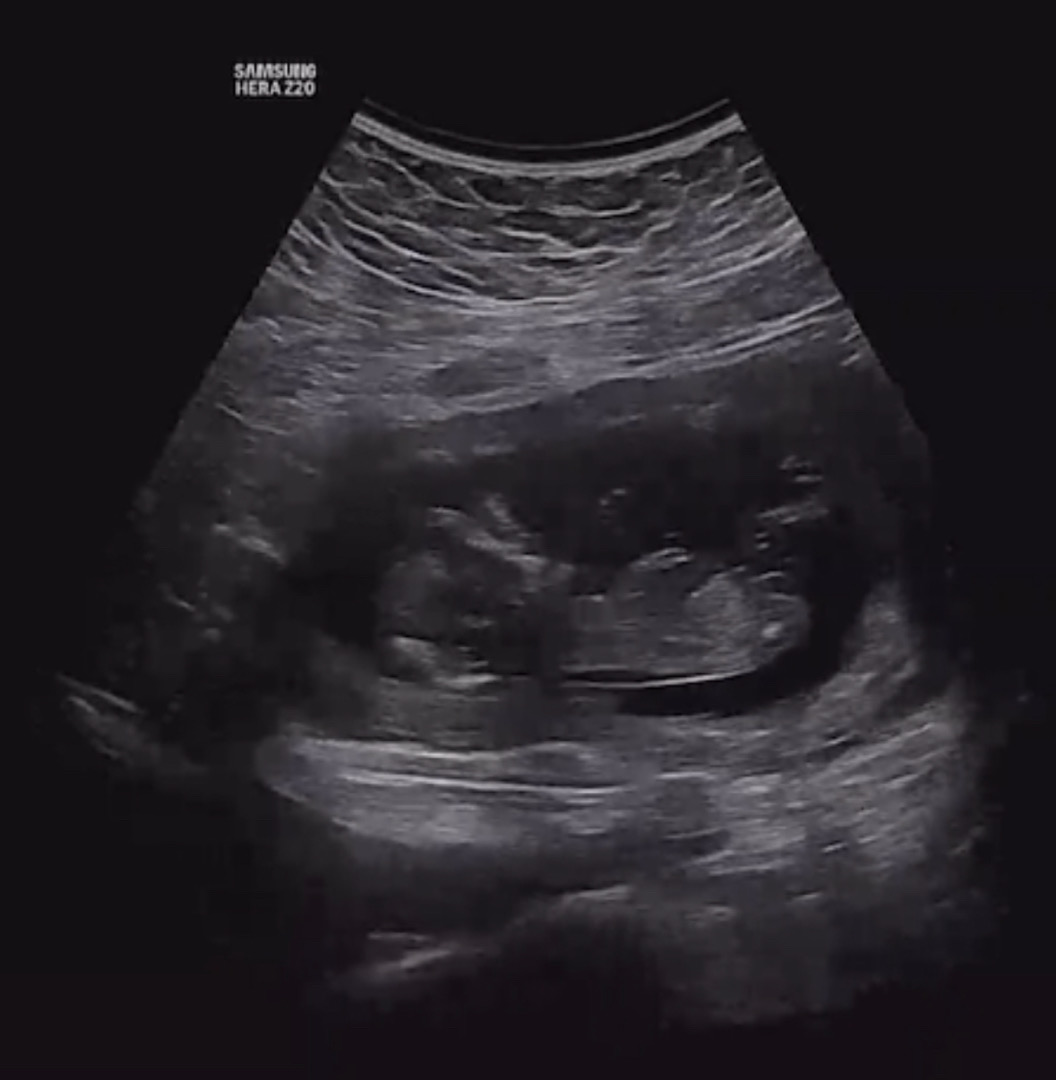

첫째 때는 12주에 딸 90%라고 들었는데 병원을 옮겼더니 여긴 아예 담에 보자구 하시네요ㅠ 딸이든 아들이든 좋지만 궁금해서 올려봅니다! 의견 부탁드립니다!

흐릿한데 딸 같아요! 저는 첫째때 요기서 각도법 적용해봤어요! https://mybabygender.com/?ref=billy

딸.....? 같긴해요^^

딸이용